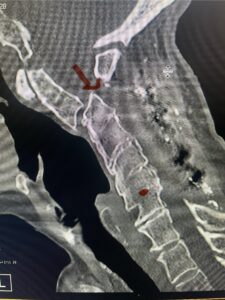

Cervical x-rays revealed a significantly increased atlanto-axial interval (Fig. 5) On review of her imaging studies it was noted that the right C2 isthmus was very thinned by the vertebral foramen (Figs 6a, b, and c) which would make an attempt at placing a C2 pars screw dangerous. A decision was made to perform an occipital-cervical fusion because only possible unilateral fixation and an extensive C1 laminectomy to be performed eliminating a fixation point if a more traditional C1-C2 was performed. Even if C1 lateral mass screws were able to be placed one could only perform a unilateral screw construct fixation to C2. We performed an occipital cervical fusion down to C4 to get enough inferior fixation and C1 laminectomy. The decompression went well. We placed a left unilateral pars screw and bilateral C3 and C4 lateral mass screws. We placed three 12 mm screws in the midline keel (Fig. 7). Postoperatively the patient had all around improvement in her symptoms and did not qualify for rehab. Her post op films at 6 weeks (Fig. 8)

Fig. 6a: Sagittal cervical CT scan demonstrating an abnormally thin right C2 isthmus prohibiting safe placement of screw (red arrow). Notice the vertebral foramen eroding the isthmus bone structure (red dot).

Fig. 6b: Sagittal cervical CT scan demonstrating normal thickness of the left C2 isthmus (red arrow)